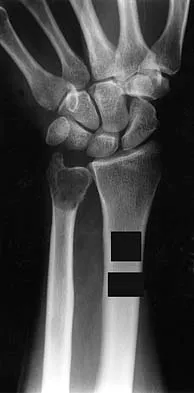

A 29-year-old man reports a 2-week history of severe neck pain after being struck sharply on the back of the head and neck while moving a refrigerator down a flight of stairs. Initial evaluation in the emergency department revealed no obvious fracture and he was discharged in a soft collar. Neurologic examination is within normal limits, and radiographs taken in the office are shown in Figures 21a through 21c. Subsequent MRI scans show intra-substance rupture of the transverse atlantal ligament. What is the most appropriate treatment option at this time?

Explanation

Dickman and associates classified injuries of the transverse atlantal ligament into two categories. Type I injuries are disruptions through the substance of the ligament itself. Type II injuries render the transverse ligament physiologically incompetent through fractures and avulsions involving the tubercle of insertion of the transverse ligament on the C1 lateral mass. Type I injuries are incapable of healing without supplemental internal fixation. Type II injuries can be treated with a rigid cervical orthosis with a success rate of 74%. Surgery may be required for type II injures that fail to heal with 3 to 4 months of nonsurgical management. Findlay JM: Injuries involving the transverse atlantal ligament: Classification and treatment guidelines based upon experience with 39 injuries. Neurosurgery 1996;39:210.